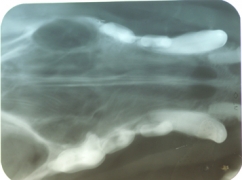

- Radiográfico (analógico y digital)

El diagnóstico clínico oral es de suma importancia ya que el plan de tratamiento y el pronóstico dependen de un certero y profundo análisis de los signos de la cavidad oral. Nuestra principal preocupación es atender los problemas que se encuentran en cavidad oral pero además siempre realizamos un detallado análisis de la función general del paciente. En nuestro centro revisamos de manera general a la mascota detectando cualquier problema sistémico. Contamos con un laboratorio de análisis clínicos en donde se realizan biometría hemática, química sanguínea, examen general de orina y pruebas para detección de enfermedades virales y de otros microorganismos. Contamos también con un laboratorio de histopatología en donde se revisa el material biológico para la detección y el diagnóstico de cambios morfológicos y lesiones en los tejidos. En lo que respecta al diagnóstico de la boca, contamos con un expediente donde se vacía toda la información dental y bucal de tal manera que mantenemos el control del tratamiento odontológico desde el inicio hasta el final y en donde el propietario o el médico que nos recomienda puede revisar en detalle toda la información recabada. Contamos con todo el instrumental y el equipo necesario para el diagnóstico de el aparato estomatognático (cavidad oral con dientes, tejidos de sostén y tejidos blandos, además de las estructuras relacionadas como articulación temporomandibular, cavidad nasal, cavidad orbitaria, etc.). Contamos con luz similar a la ultravioleta para diagnóstico de lesiones dentales por transluminación, pulpómetro para diagnóstico de vitalidad pulpar, localizador de ápices para tratamiento de conductos y equipo radiográfico tanto analógico como digital.